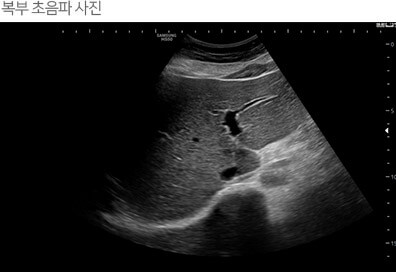

실생활에서 간수치 낮추는 방법

간강검진을 한 후에 간수치가 높게 나왔다는 결과를 듣고 걱정하는 분들이 주변에 많이 있는데요.

침묵의 장기라고하는 간은 전조증상이 거의 없고 어느 정도 병이 진행되어 되었을 때 증상이 나타나기

때문에 그만큼 간관리, 건강검진을 통해 점검이 중요합니다.